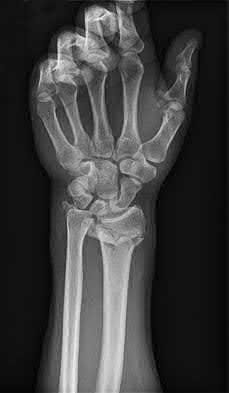

A 51-year-old female presents with an acute inability to extend her thumb, four months after she was treated with cast immobilization for a minimally-displaced distal radius fracture. What is the most appropriate treatment at this time?

A rare complication of non-displaced or minimally displaced fractures of the distal radius treated with a cast is a delayed rupture of the extensor pollicis longus (EPL) tendon. The EPL is the primary extensor of the interphalangeal joint of the thumb and also assists with metacarpophalangeal extension.

Extensor indicis proprius transfer to the EPL is the most widely used and reported treatment for this condition.

Magnussen et al. reviewed results of EIP transfer following ruptures of the EPL, with 19/21 good results. None of the cases had any loss of independent index finger extension although index extensor strength reduced to half of that of the contralateral side.

Hove et al. reported a similar satisfaction rate following treatment of 15 patients. In his series of 4,400 distal radius fractures treated over a 5 year period, the incidence of delayed tendon rupture following distal radius fracture was 0.3 percent.